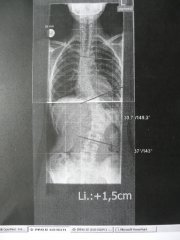

Wow, super beobachtet. Die untere Pelotte IST zu großflächig und die obere zu mickrig. Beides wird morgen endlich korrigiert. Dr. Landauer hat sich 1 Stunde für uns Zeit genommen. Er meinte, dass das momentane Korsett mal optimal sitzen muss und dann bekommt Ramona ein Neues. Das "alte" kann man dann nicht weiter aufpelottieren.minimine hat geschrieben:Ich finde, wenn man die Bilder vom Korsett und auch das Röntgenbild anguckt, dann sieht die untere Pelotte ziemlich großflächig aus, die obere Pelotte dafür aber ziemlich mickrig. Bei meinem Korsett ist das eher umgedreht, die obere Pelotte ist von der Fläche her größer als die untere.

Außerdem bekommt sie eine 1 cm Schuheinlage. Zum Thema Primärkorrektur hat er nicht viel gesagt.......

Anbei ein Röntgen ohne Korsett (ich weiß, es ist nicht gerade "berauschend") im Unterschied mit Korsett!!

Ich finde, wenn man die Bilder vom Korsett und auch das Röntgenbild anguckt, dann sieht die untere Pelotte ziemlich großflächig aus, die obere Pelotte dafür aber ziemlich mickrig. Bei meinem Korsett ist das eher umgedreht, die obere Pelotte ist von der Fläche her größer als die untere.